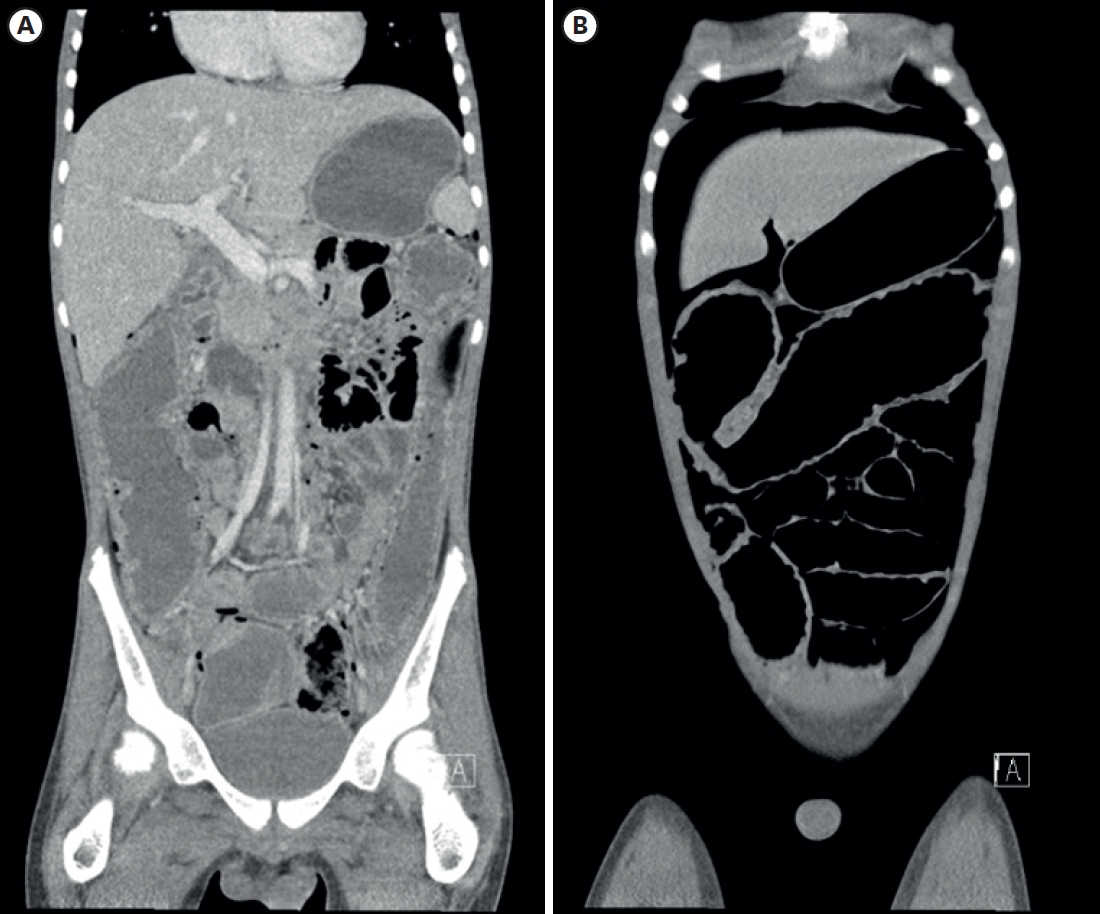

A 13-year-old boy was referred to the pediatric emergency room due to suspected bowel perforation and panperitonitis. He was hospitalized for diarrhea at a local clinic 8 days prior and referred to another ER the day before. Computerized tomography (CT) scans had demonstrated diffuse dilatation of colon with pneumatosis intestinalis suggestive of toxic megacolon (Fig. 1). His underlying conditions included autism and developmental delay (mental retardation). Although the patient displayed facial dysmorphism and inability to flex both 5th finger proximal interphalangeal joints, no genetic study or chromosomal microarray test had been performed before. At admission, a review of systems revealed histories of fever, cough, nausea, hematochezia, and abdominal pain.

Physical examination of the patient marked abdominal distension and tympanic bowel percussion sound with diffuse abdominal tenderness and rebound tenderness. Abdominal X-ray taken on the operative day suggested bowel perforation. CT scans demonstrated massive amounts of free air, leading to a strong suspicion of pneumoperitoneum and bowel perforation. Chest X-ray imaging found no active lung lesions. Taking the patient’s underlying conditions into account along with physical and radiological findings, UC with colon perforation was diagnosed. The patient then underwent a subtotal colectomy with end ileostomy.

Fig. 1.

A 12-year-old male patient with diarrhea, abdominal pain, and fever. (A) CT image showing diffuse dilatation of the colon with extensive pneumatosis intestinalis, (B) CT image showing free air in abdominal cavity.

CT, computerized tomography.

Fig. 1. A 12-year-old male patient with diarrhea, abdominal pain, and fever. (A) CT image showing diffuse dilatation of the colon with extensive pneumatosis intestinalis, (B) CT image showing free air in abdominal cavity. CT, computerized tomography.